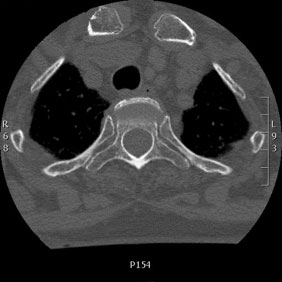

Tomografía computarizada Columna

< Volver a "Tomografía Computarizada (TC) con Inteligencia artificial"Con esta prueba valoraremos la patología de las vertebras, fracturas, hernias, protusiones discales,…